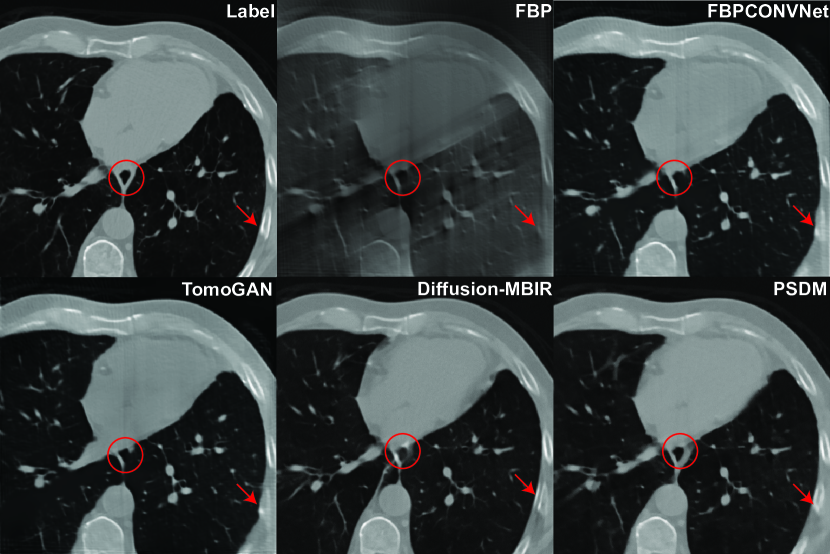

Refer to caption

Figure 5: Reconstruction results from the AIMI COCA dataset with 120 views using different methods. The display window is [900900-900 100010001000] HU.

4.2.1 Stanford AIMI COCA results

To advance our clinical dataset evaluation, the Stanford AIMI COCA dataset[42] is employed. The COCA dataset is a compilation of 789 gated CT scans, with each scan corresponding to an individual patient. On average, every patient contributes roughly 50 image slices, and each image slice possesses a resolution of 512 x 512 pixels. The NCSNPP model is trained with data from 60 patients, totaling approximately 3,400 image slices. Apart from the image size, all other parameters remain consistent with the simulation training. The reconstruction results from 120 views appear in Fig. 5. Significantly, our proposed method produces images of enhanced quality characterized by prominent features and sharp image boundaries. This is especially discernible in the areas and structures underscored by red circles and arrows. In contrast, other algorithms tend to obscure certain details and introduce blurring.